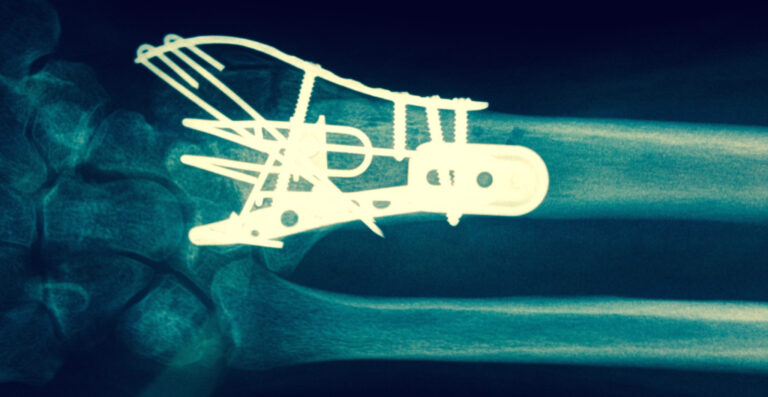

Surgical Approach

When there is displacement or the Broken Wrist Colles’ Fracture cannot be stabilised following manipulation then surgery may be required. The Hand Therapists, Physiotherapists and Occupational Therapists at Action Rehab Hand Therapy Clinic are experienced in treating post surgical Broken Wrists. It is important that you seek Hand Therapy following your wrist surgery in order to limit your post operative complications, increase your function and return to sport or work sooner.

See below the two treatment approaches for a patient who has broken wrist.